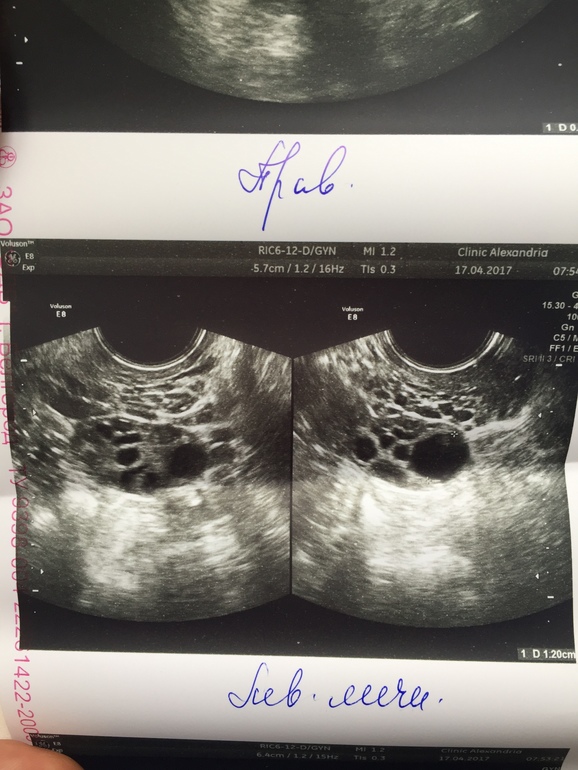

Созревание фолликула в яичнике: этапы и процессы